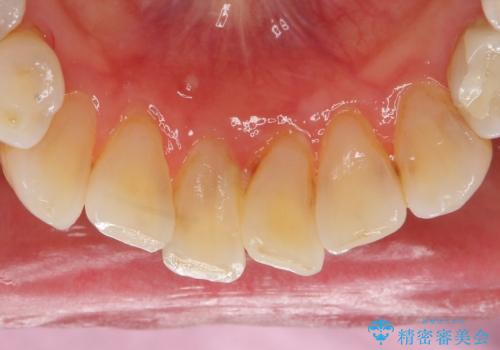

口腔内を精査したところ、右上のブリッジの内側(口蓋側)がかけており、下の前歯(右下1)には唇舌側に瘻孔を伴う大きな根尖病変ができていました。

右上のブリッジ(右上④3②)のやりかえと、下の前歯(右下1)の根管治療を行った後セラミッククラウンによる補綴治療を行いました。